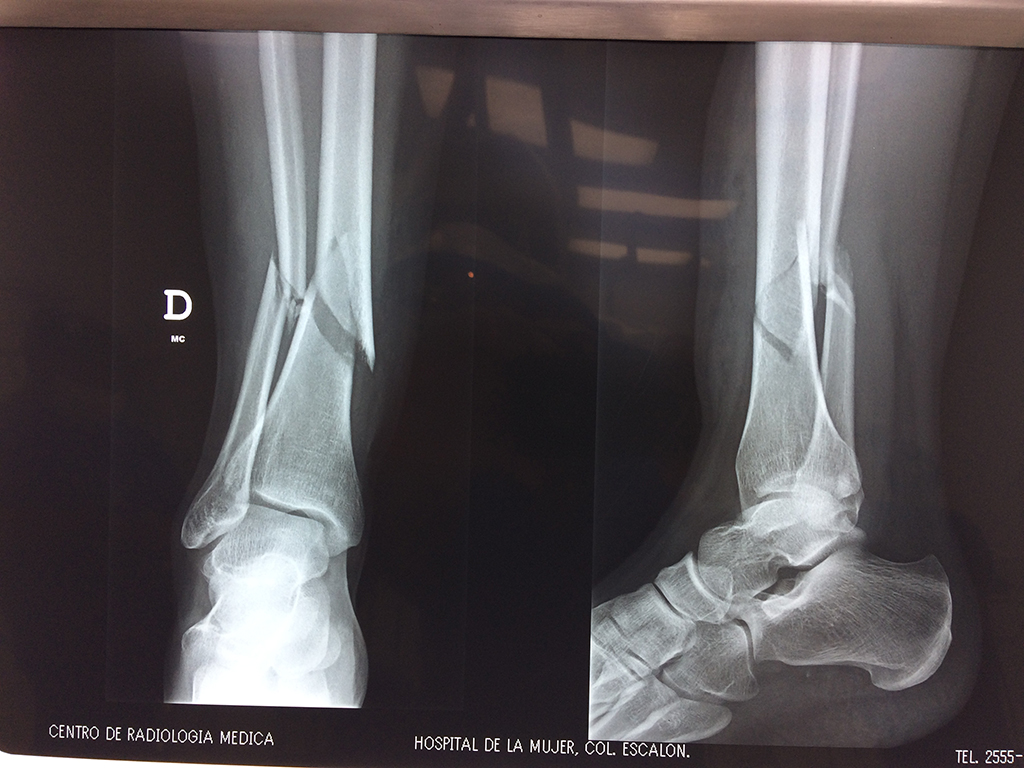

Cirugías de Calcaneo - Perone y Tibia

Aunque cada uno de estos huesos puede fracturarse por separado, normalmente la rotura es una lesión que se produce de forma conjunta

La mayor parte de las roturas implican a la parte proximal del hueso (parte del hueso próximo a la rodilla) o a la parte distal (parte del hueso cerca del tobillo).

Debido a la fina cobertura de piel que recubre la tibia y el peroné, las fracturas generalmente son abiertas, es decir, el hueso roto rasga la piel, atravesándola. Las fracturas de tibia y peroné generalmente se producen por un fuerte impacto o torsión.